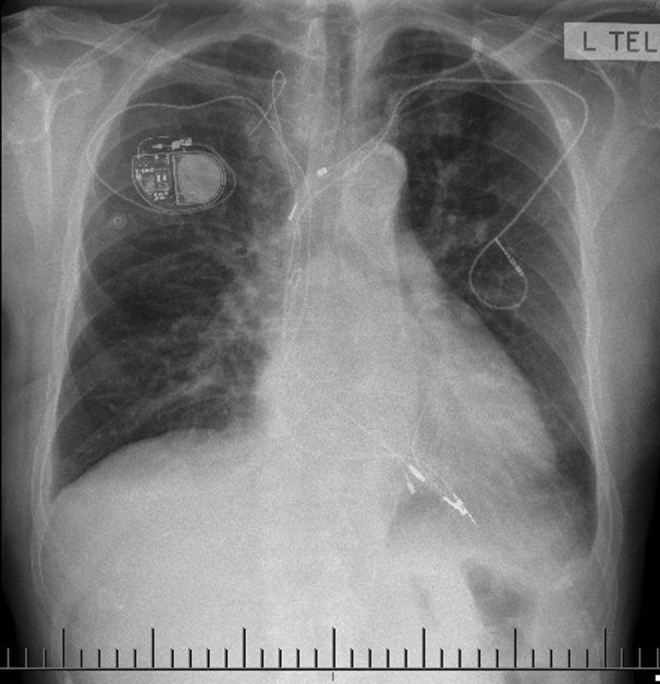

Figure 3.

Chest radiograph October 2021 following tenth generator implant.

In June 1995 replacement indictors on the Activatrax were detected at a routine follow-up and the device was electively replaced with a Medtronic Legend 8416 (Figure 2). After 13 years, normal battery depletion triggered elective replacement to a St Jude Verity ADX 5156 (Figure 2). At this generator change a visible insulation breach was noted at the lead yoke and although the lead was alerted for polyurethane degradation, given that all parameters were within normal limits and a significant volume of hardware was already in situ, the breach was repaired with a splice kit. When scheduling elective box change for normal battery depletion in October 2021, it was decided replacement was necessary given the lead age of 36 years. With the right sinus now dry, a Medtronic 5076 was successfully implanted via right cephalic access and connected to a Medtronic Azure single-chamber pacemaker (Figures 2 and 3).